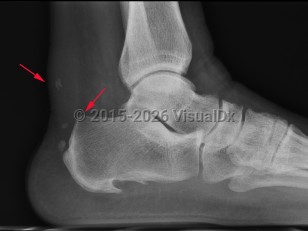

Haglund deformity is enlargement of the posterosuperior tuberosity of calcaneus. Retrocalcaneal bursitis is inflammation of the space between the anterior aspect of Achilles tendon and posterior aspect of calcaneus.

Insertional Achilles tendonitis is pain and tendon thickening at insertion of the Achilles tendon, wherein repetitive trauma leads to inflammation followed by cartilaginous, bony metaplasia.